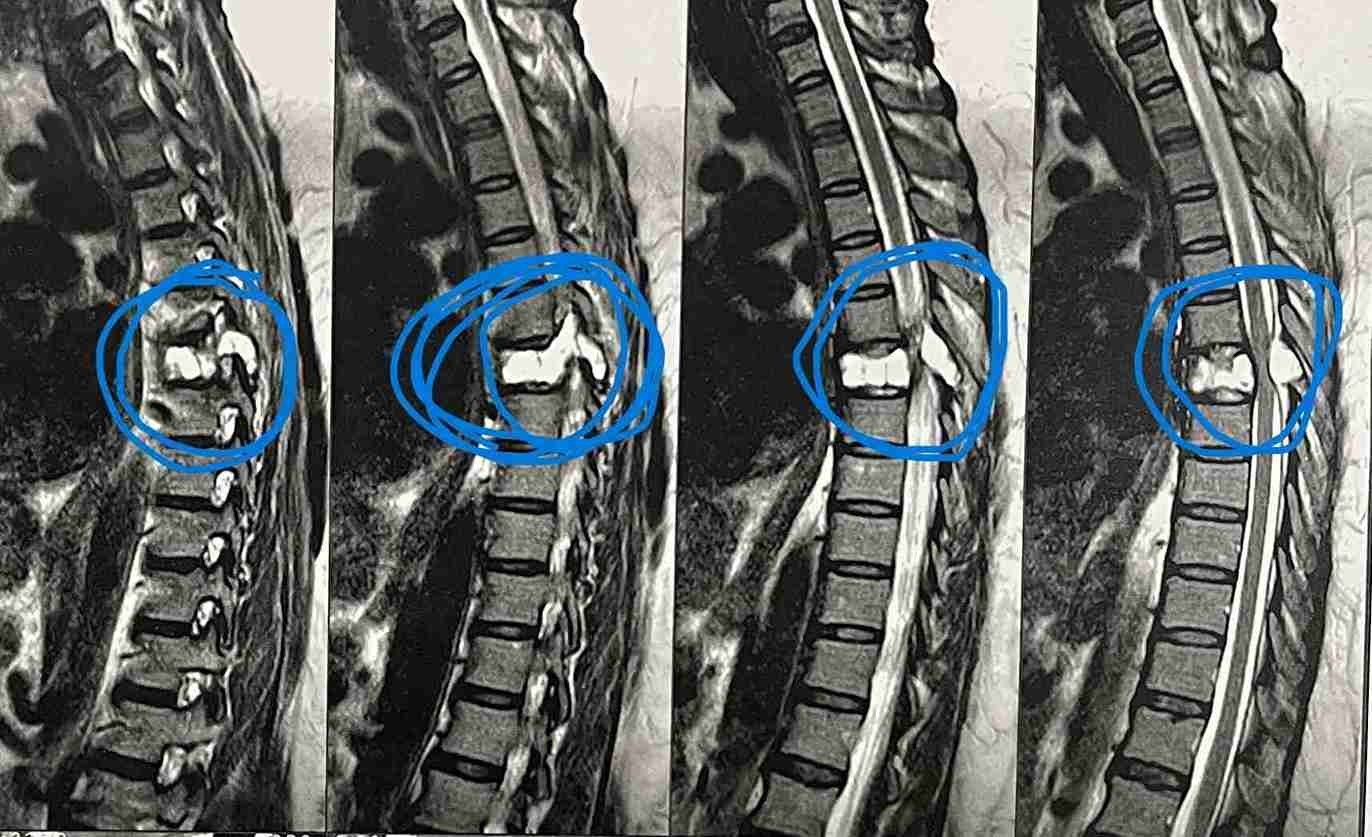

بعد عمل الاشعات تبين وجود ورم التكيس الدموي المتمدد بالفقرة الصدرية السادسة.

وذلك موضح بصور الاشعات قبل وبعد الجراحة . وقد تحسنت المريضة واستعادت كامل الوظايف العصبيىة واصبحت تمارس حياتها بصورة طبيعية.

و الأكياس العظمية المتمددة هي نوع من الافات المرضية الوعائية الغير خبيثة تشبه الورم وتتكون من قنوات مملوءة بالدم متمددة فتؤدي الي ضغط علي الانسجة المحيطة.

وقد تؤدي طبيعتها التوسعية التمددية إلى الألم والالتهاب واختناق الاعصاب والنخاع الشوكي بسبب هذا الضغط.